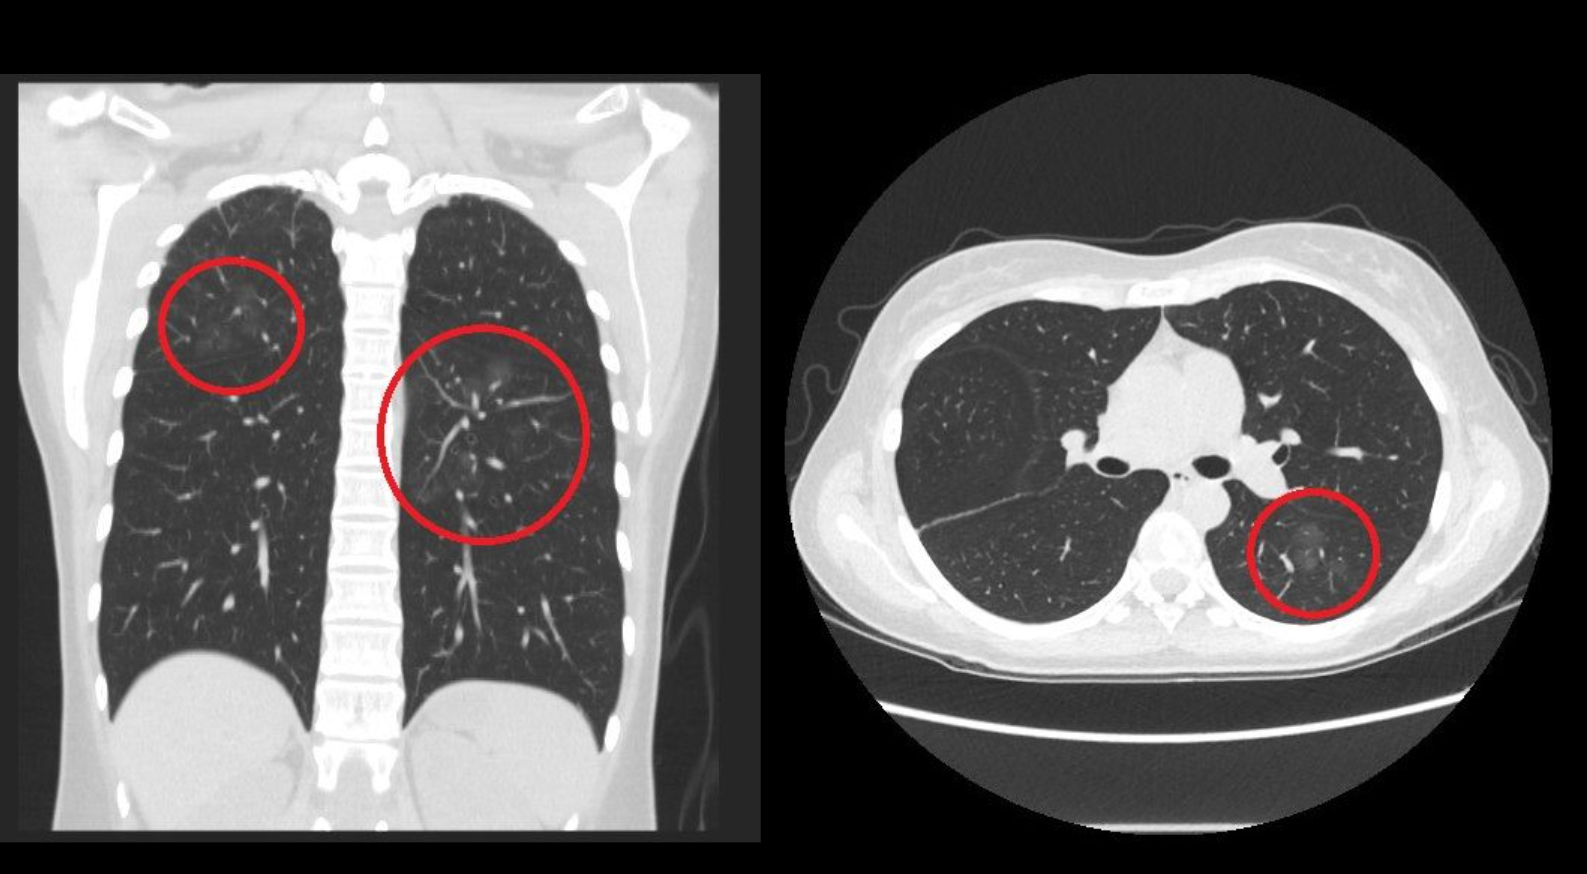

【肺結節/教師/老師/吸煙/咳嗽/工作習慣/消失/癌症/患癌】台灣胸腔內科醫生蘇一峰在Facebook發帖,指一名30多歲的幼稚園教師沒有抽煙,也沒有咳嗽症狀,到醫院自費做低劑量電腦斷層掃描檢查,卻發現有10個「毛玻璃」的肺結節,其中大的肺結節更達1厘米以上。

該患者隨即向蘇一峰求診,他仔細詢問對方病史,該患者透露因工作關係,經常要使用漂白水消毒。對此,蘇一峰判斷可能是化學性肺炎,為漂白水吸入造成的肺炎,並非癌症的肺結節。

他處方適當藥物,並囑咐對方要注意減少漂白水吸入,1年後10個肺結節均消失。